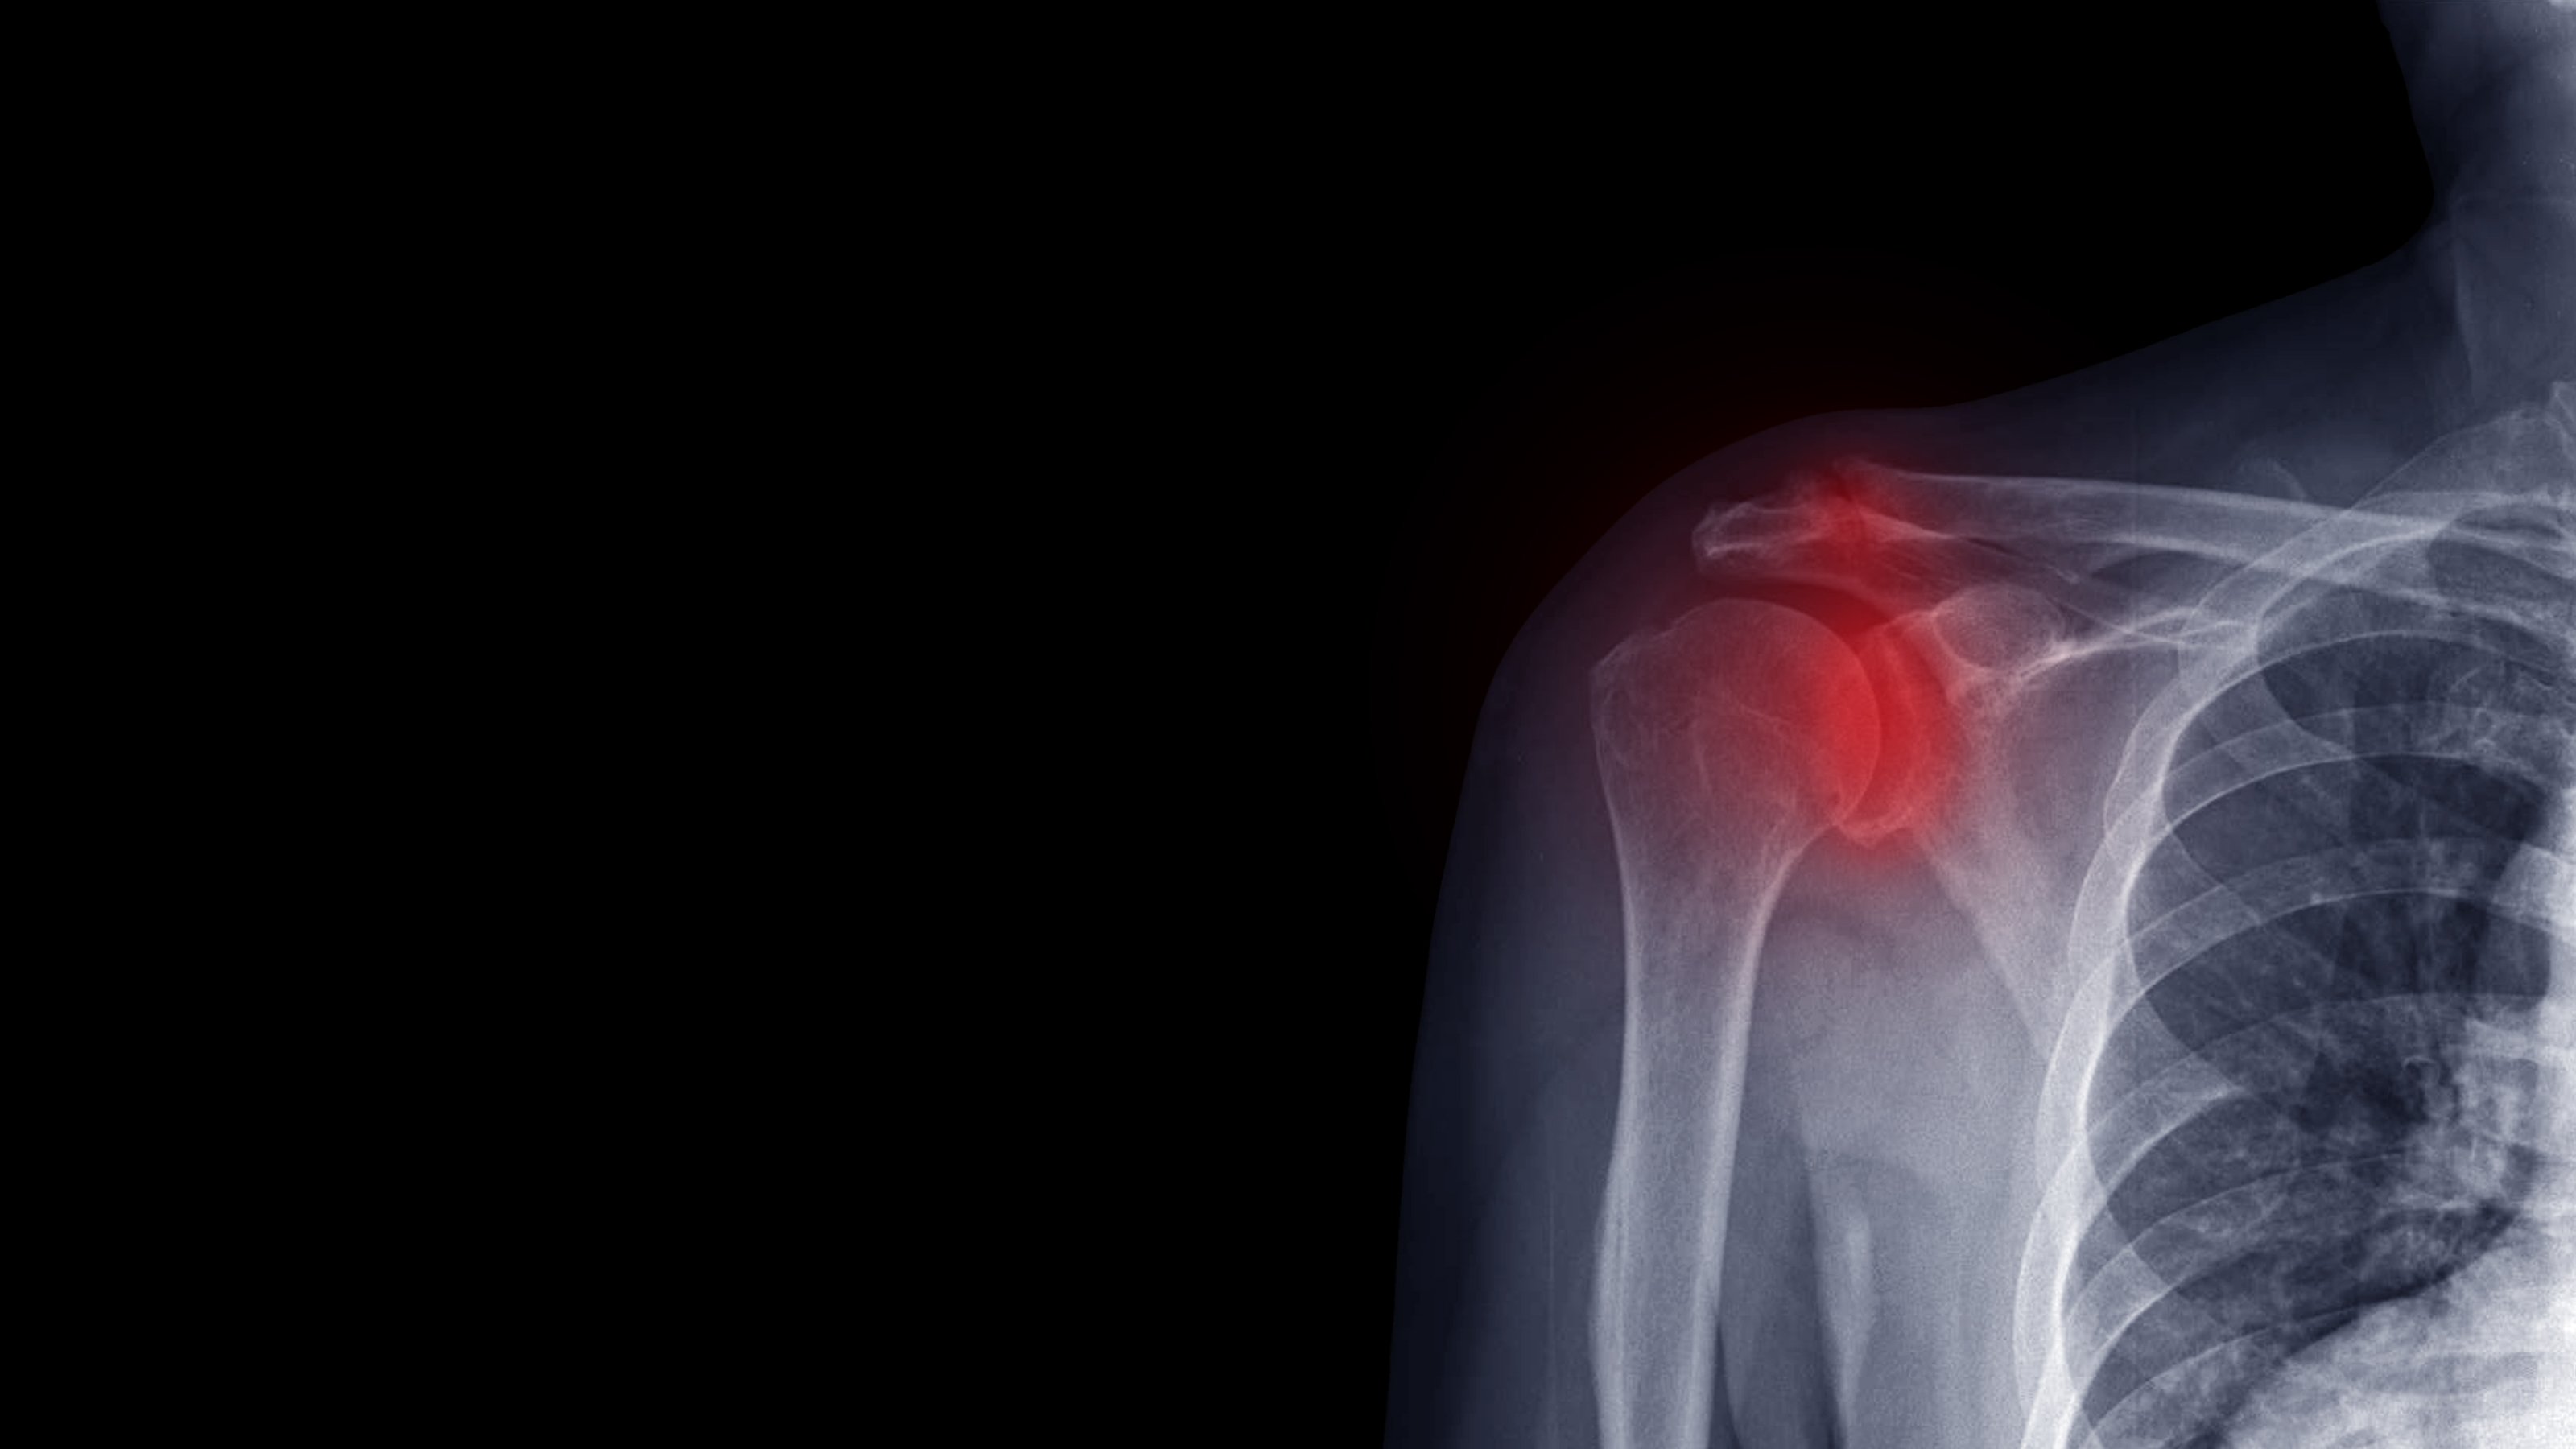

Рентген плеча: примеры снимков и их расшифровка